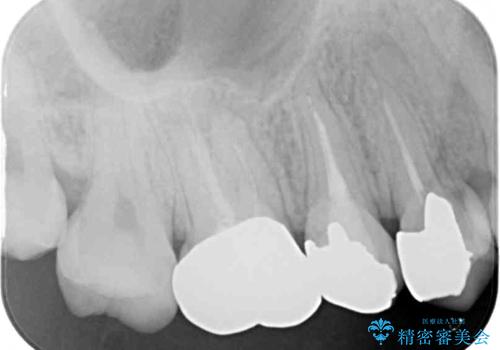

- 笑ったときに見てしまう上顎奥歯の銀歯を気にして来院された患者様です。

折角セラミッククラウンを装着するので、根管治療を行った後に補綴治療を行うこととしました。

他にも目立つ銀歯がありましたが、最も気にしている2本を優先して行うこととしました。